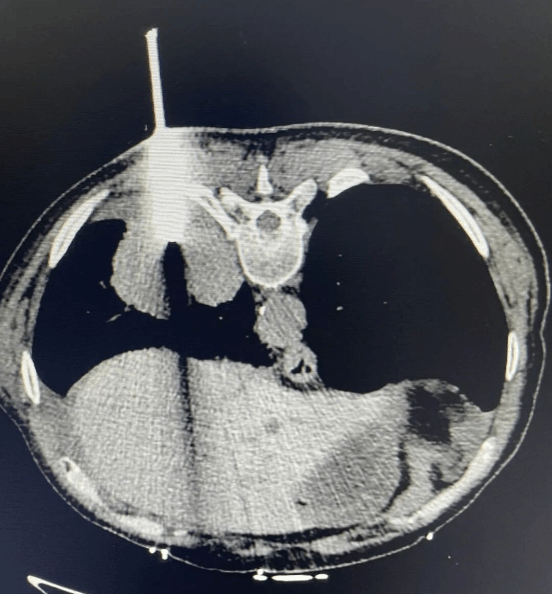

在CT精准引导下,冷冻活检全程创伤极小,患者恢复快,并发症发生率与传统穿刺相当,兼顾了诊断效能与医疗安全。

• 冷冻活检操作中,医护人员细致操作,将完整的病变组织顺利取出,为病理诊断提供坚实保障。